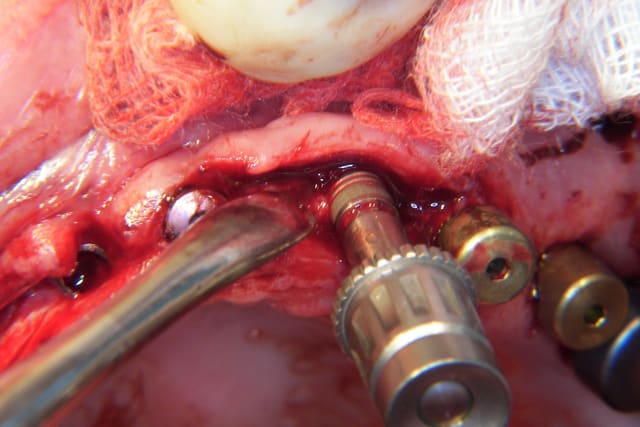

Effectivement Growler, la crête atrophique à la mandibule est souvent dense (type 1 à 2); il est difficile réaliser une mobilisation du volet vestibulaire avec les seuls osteotomes. Pour augmenter l'élasticité du volet osseux vestibulaire, une incision longitudinale basale de décharge es très souvent nécessaire en plus des incisions verticales et crestale. Cette incision longitudinale augmente la résilience et soulage la mobilisation du volet osseux vestibulaire. Ce dernier peut très facilement après mobilisation être transvissé et fixé par des vis d'osteosynthèses classiques.

Il est à mon avis préférable d'obtenir un trait de fracture propre et maitrisé plutôt qu'un volet vestibulaire fragilisé, traumatisé et abimé.

Splitting mandibulaire nnrckm - Eugenol